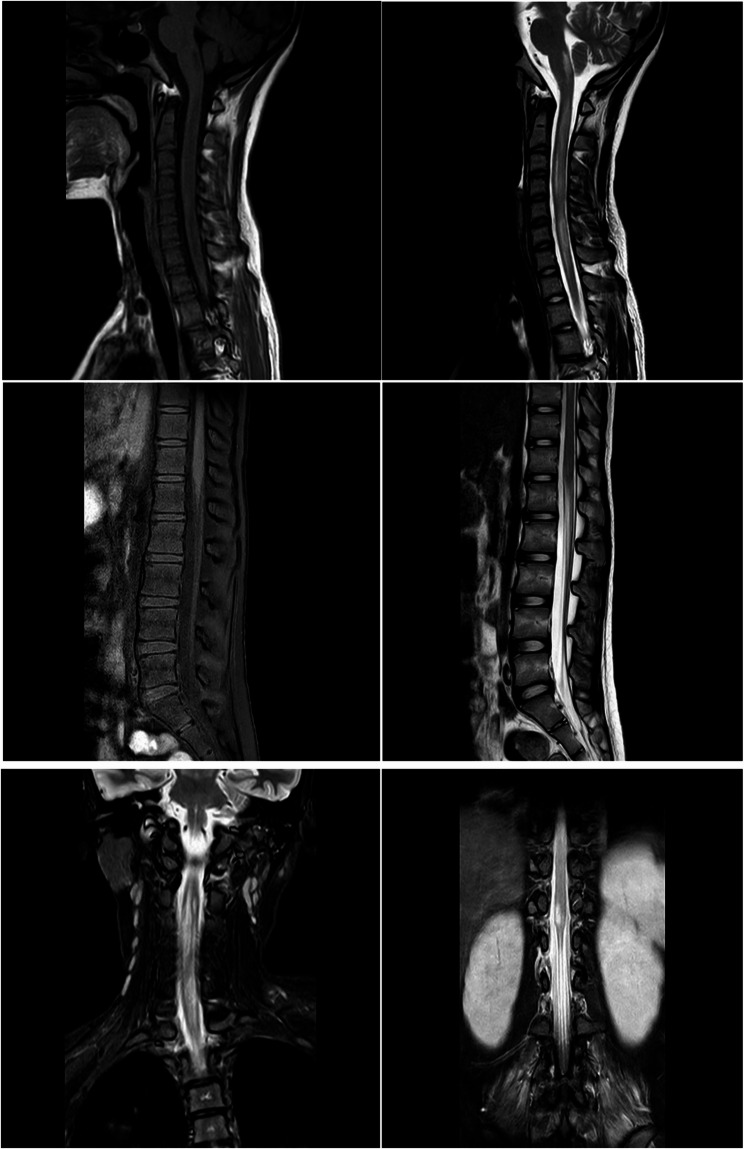

Mycoplasma pneumoniae infection and concurrent aquaporin-4-positive neuromyelitis optica spectrum disorder: a case report and literature review.